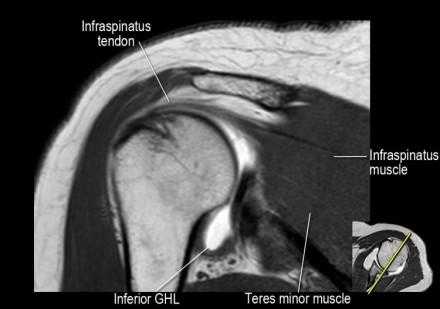

Изображение задних отделов плечевого сустава.

Отображены надостная, подостная и малая круглая мышцы и их сухожилия. Все они прикрепляются к большому бугорку плечевой кости. Сухожилия и мышцы манжеты вращателей участвуют в стабилизации плечевого сустава во время движения. Без манжеты вращателей головка плечевой кости частично сместилась бы из суставной впадины, уменьшив силу отведения дельтовидной мышцы (мышцы вращательной манжеты координирует усилия дельтовидной мышцы). Повреждение манжеты вращателей может привести к смещению головки плечевой кости кверху, в результате вызвая высокое стояние головки плечевой кости.